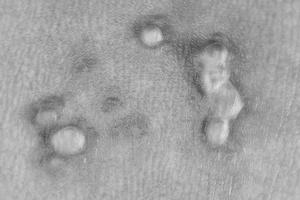

Половые бородавки – маленькие, мягенькие, беленькие образования на тонкой ножке. Со временем они разрастаются и достигают размера петушиного гребня, что сильно осложняет ведение половой жизни.

Врачеватели Древней Греции дали ей название «кондиломы», или половые бородавки. Выявлять папиллома-вирус человека научились в конце 60-х годов нашего столетия в связи с открытием электронной микроскопии. С этого же периода отмечается неудержимое распространение заболевания по планете. В середине 70-х ученые-медики считали, что приблизительно 1,2 % жителей Земли страдают от бородавок, по прошлогодней же статистике каждый 6 землянин болен кондиломатозом. Все начинается, как ни странно, с полового контакта с носителем вируса: несколько минут чувственного наслаждения и... через несколько месяцев на нежной и чувствительной коже женских гениталий: половых губках, влагалище, шейке матки, вокруг наружного отверстия мочеиспускательного канала или заднего прохода (все зависит от изобретательности в интимных забавах), – вырастают маленькие, мягенькие, беленькие бородавочки на тонкой ножке.

Проходит еще год-другой, нежные и невинные бородавочки разрастаются, превращаясь в образования, напоминающие видом своим гребешок

петуха или цветную капусту. Трансформирующиеся кондиломы сильно осложняют жизнь больного: они мешают ходить, при актах любви отрываются, вызывая боль и кровотечение, затрудняя, в известной степени, половую жизнь. Вот тогда-то пациент и приходит к врачу, который выписывает пилюли и «уколы», усиливающие иммунитет, или выжигает эти вредоносные образования лазером или жидким азотом. После такого лечения от бородавок не остается и следа. Нужно особо отметить, что приблизительно у трети людей бородавки «рассасываются» самостоятельно. Осложнения: если бы бытие наше было бы устроено слишком просто, то, согласитесь, не стоило бы и жить! А посему эпопея с половыми бородавками продолжается. При отрыве бородавок может возникнуть кровотечение.